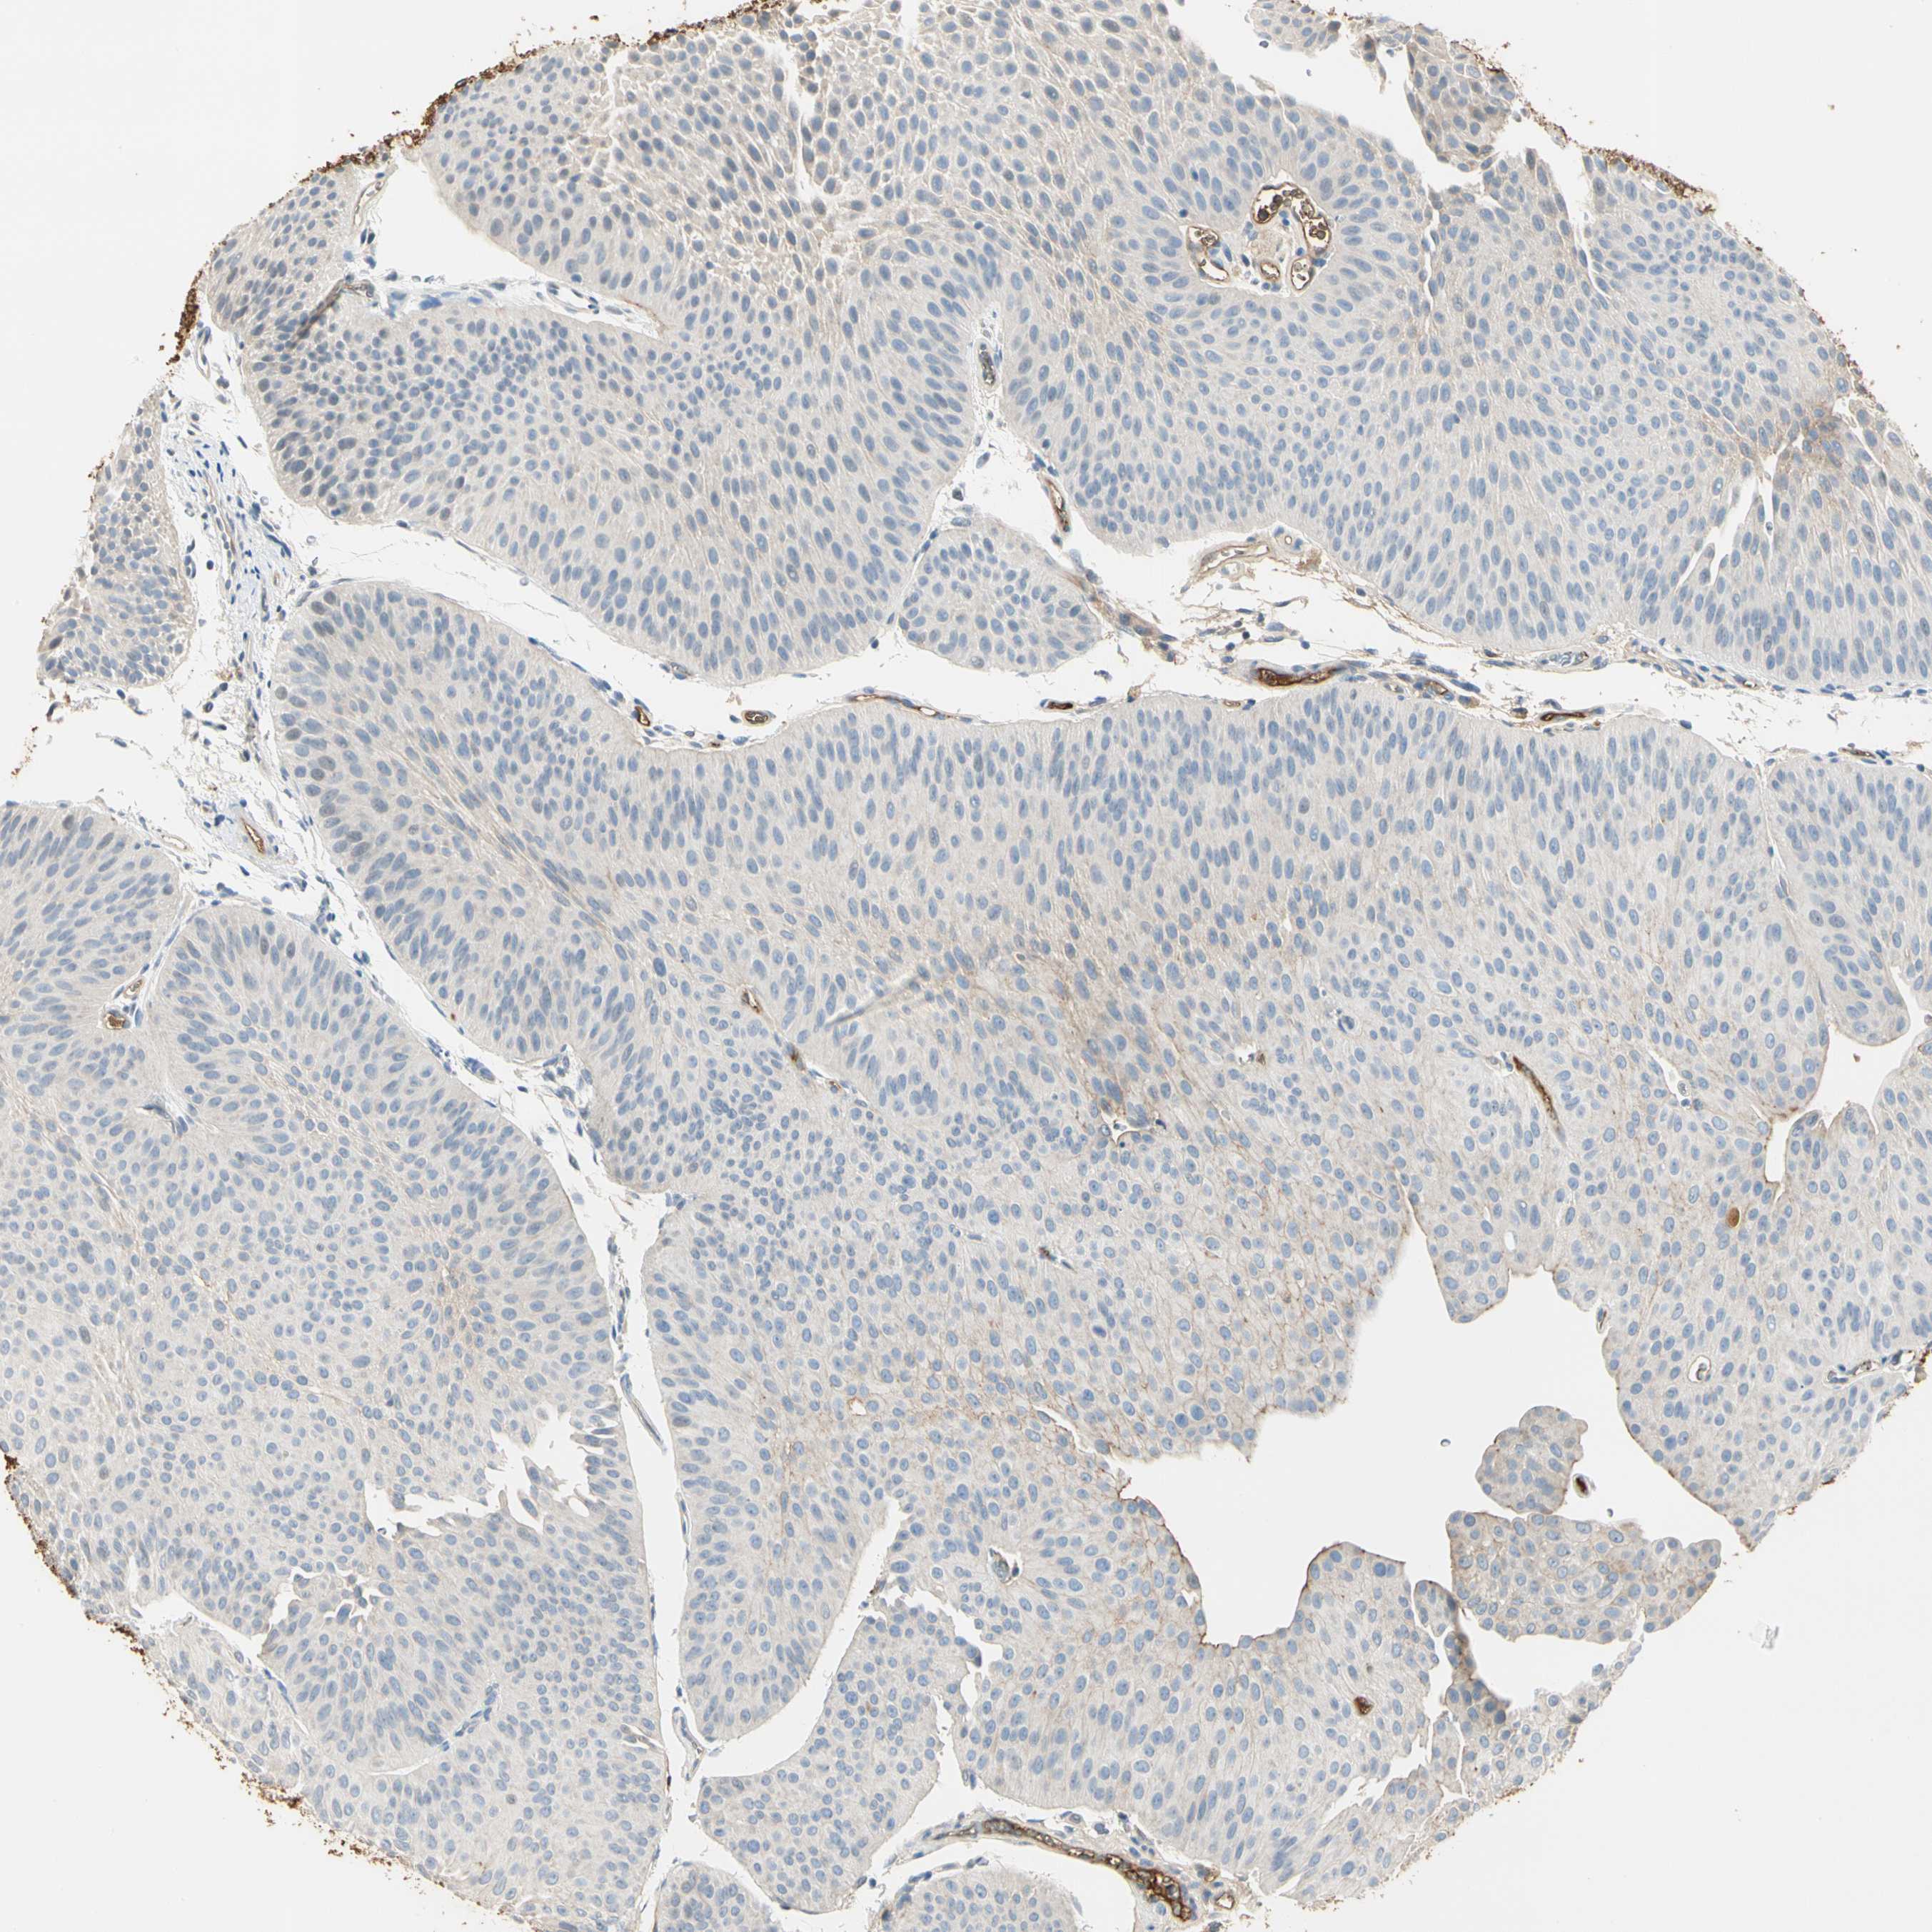

UROTHELIAL CANCER - Protein expressioni

A mouse-over function shows sample information and annotation data. Click on an image to view it in a full screen mode. Samples can be filtered based on level of antibody staining by selecting one or several of the following categories: high, medium, low and not detected. The assay and annotation is described here.

Note that samples used for immunohistochemistry by the Human Protein Atlas do not correspond to samples in the TCGA dataset.

Antibody stainingi

Antibody staining in the annotated cell types in the current human tissue is reported as not detected, low, medium, or high, based on conventional immunohistochemistry profiling in selected tissues. This score is based on the combination of the staining intensity and fraction of stained cells.

Each image is clickable and will lead to virtual microscopy that enables deeper exploration of all samples and also displays staining intensity scores, fraction scores and subcellular localization as well as patient and tissue information for each sample.

Antibody HPA008069

Antibody CAB078183

Staining

High

Medium

Low

Not detected

Intensity

Strong

Moderate

Weak

Negative

Quantity

>75%

75%-25%

<25%

None

Location

Nuclear

Cytoplasmic/membranous

Cytoplasmic/membranous,nuclear

Urothelial carcinoma, Low grade

Urothelial carcinoma, High grade

Urothelial carcinoma, NOS